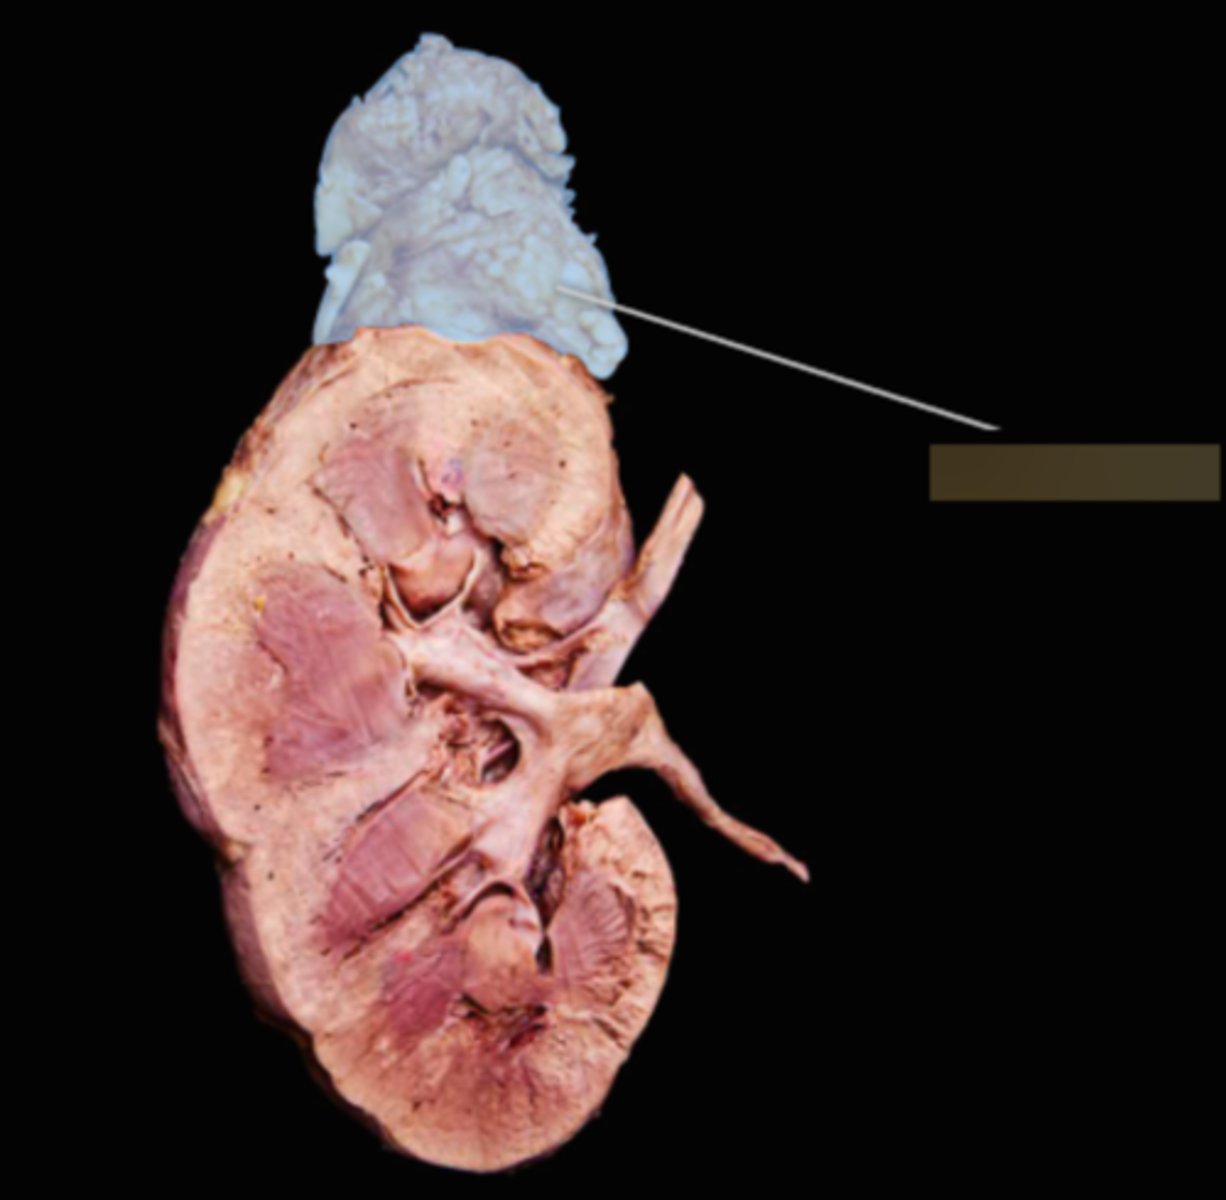

Right Adrenal Gland

Left Adrenal Gland

Right Kidney

Left Kidney

Renal Capsule

Renal Cortex

Renal Medulla

Papilla

Renal Column

Minor Calyx

Major Calyx

Renal Pelvis

Renal Hilum